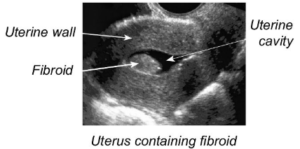

Images of SIS: Saline in the uterine cavity looks like black or “empty” space. A fibroid (benign tumor) can be seen in the image on the bottom.